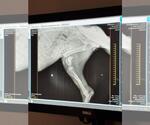

Dog Breed: Doberman Pinscher / Mixed. Trinity - A Doberman X puppy- A Survivor Soon Ready for Her Forever Home Meet Trinity, a 5-month-old Doberman mix who, despite her tough beginnings, is full of spirit, resilience, and love. Found days later in the same area as her likely sibling, Quinn, Trinity has had a difficult start. Not only did she suffer a severely broken leg, but her emaciated little body was also covered in bite wounds—likely from other animals. These injuries are a testament to the harsh reality she faced on her own before being rescued. X-rays revealed that her leg was broken in four places, and the bones are severely infected. Sadly the vet feels, the injury is beyond repair, and after careful consideration, her leg will be amputated to help her heal. Trinity is no stranger to overcoming obstacles. Even through her pain and uncertainty, she remains a sweet and affectionate pup, eager to bond with those around her. Adopting Trinity: A Rewarding Journey Once Trinity has fully recovered from her surgery and rehabilitation, she will be ready to begin a new chapter of her life with a family who will provide the love and care she deserves. Trinity is a survivor, and she is sure to make a loyal, loving companion. While she may be missing one leg, her heart is as big as ever, and she’s expected to adapt quickly to her new way of life—still full of playful energy and the affectionate nature that makes her such a special pup. If you are looking for a brave, loving, and resilient pup to welcome into your home, Trinity could be the perfect fit for you. She will need an environment that can support her during her recovery but also a place where she can live out her life as an active and joyful member of the family. Trinity’s playful personality and loving nature will be the perfect addition to the right home, and she’s sure to return the love tenfold. This girl is everyone's friend! What Trinity Needs in Her Forever Home: A patient and understanding family ready to support her through her recovery and beyond. A home with a secure yard where she can play safely and get the exercise she needs. A calm and loving environment where she can heal physically and emotionally. A family willing to continue her training and make sure she gets the care she needs for her leg amputation. How You Can Help: We are still seeking donations to cover Trinity’s medical expenses, including her surgery and rehabilitation. Your support will help her recover and thrive as she prepares for adoption. Once she’s fully healed, Trinity will be ready to give her new family all the love and companionship they could ever need. If you are interested in adopting Trinity or would like to learn more about how you can help, please reach out to us. She’s a survivor, and with your help, she can have the life she was always meant to live—full of love, care, and happiness. A Reminder: Trinity’s story is a heartbreaking yet inspiring reminder of why it’s so important to spay and neuter pets. It’s also a powerful example of how every little bit of love and support can change the life of an animal in need. Will you be the one to offer Trinity her second chance? She’s waiting for her forever home—and that home could be with you. .uniteddobermanrescue United Doberman Rescue Adoption Process Application Submission: Complete the adoption application thoroughly. Incomplete applications may be denied.(uniteddobermanrescue) We are 100% volunteer, please read adoption requirements BEFORE reaching out to us. Home Visit: A volunteer will schedule a home visit to assess the environment and discuss your expectations. All household members, including children, must be present.(uniteddobermanrescue) Veterinary Reference Check: Provide contact information for your current veterinarian. All existing pets must be spayed/neutered, current on vaccinations, and on heartworm preventative.(uniteddobermanrescue) Meeting Dogs: Once approved, you'll have the opportunity to meet adoptable dogs in their foster homes. If you have a resident dog, consult with the foster about bringing them along. Adoption Finalization: If a suitable match is found, you'll sign an adoption contract and pay the adoption fee. Due to COVID-19 precautions, same-day adoptions are currently permitted. Key Adoption Policies Age Requirement: Adopters must be at least 21 years old and reside in the home where the dog will live.(uniteddobermanrescue) WE do NOT ship our dogs ever!!! Children: Adult dogs are not placed in homes with children under 6 years old. Puppies may be considered for such homes if a fenced yard is present.(uniteddobermanrescue) Living Arrangements: Dogs must live indoors and not be left unattended outdoors. Training Commitment: Adopters should be prepared to continue training and socialization. Formal obedience classes are encouraged.(uniteddobermanrescue) Health Considerations: Dobermans are prone to certain health issues. Adopters should be financially prepared for potential veterinary expenses and consider pet insurance. Return Policy: If you're unable to keep your adopted dog, UDR requires the dog be returned to them, except in cases involving aggression or biting.(uniteddobermanrescue) {s8319code4181/} We follow the Doberman Pinscher Club of America's Code of Ethics. For more information visit the DPCA at .dpca